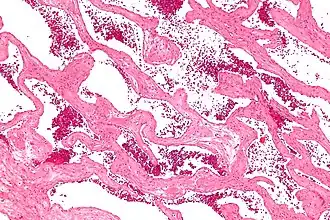

El cavernoma, llamado también angioma cavernoso o malformación cavernosa, es una malformación vascular bien circunscrita, compuesta por un endotelio grueso de forma sinusoidal, con lo que adquiere un aspecto de mora. Las células del endotelio son parecidas a las células que forran los vasos sanguíneos normales, pero faltan las otras capas que se encuentran en las paredes de un vaso sanguíneo normal. Las anomalías en la pared de estos vasos los predisponen a las hemorragias.